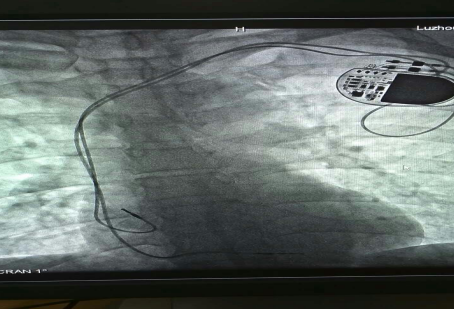

已安裝好的起搏系統(tǒng)

在征得患者及家屬的同意后,我院為其實(shí)施了雙腔永久心臟起搏器植入術(shù),該手術(shù)在瀘州市市屬醫(yī)院中率先使用磁共振兼容起搏電極,為患者未來有可能接受的磁共振檢查創(chuàng)造了條件。